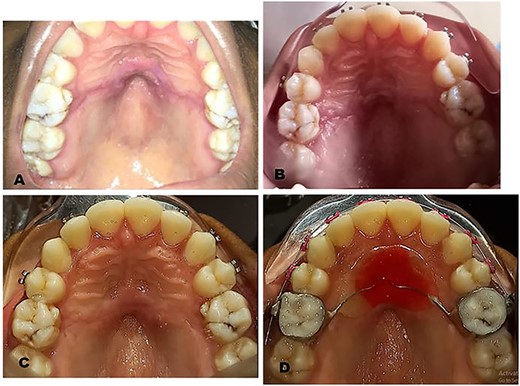

A 19-year-old female presented at the Orthodontic clinic of the Lagos University Teaching Hospital, Lagos, Nigeria with a complaint of dental malocclusion. Her first presentation to the orthodontics clinic, Lagos University Teaching Hospital was 5 years prior when she received orthodontic treatment in the form of upper and lower preadjusted edgewise fixed orthodontic appliance and Nance palatal arch appliance. However, patient did not keep to her follow-up orthodontic appointments for availability reasons and presented back to our orthodontic clinic 5 years after initial treatment for continuation of treatment. On intraoral examination, the hard palate appeared thick and fibrotic but with an overall clinically healthy appearance. The bands of the Nance palatal arch appliance were fixed satisfactorily to the upper first molars but the looped 0.9 mm hard stainless steel wire and the acrylic button of the Nance palatal arch appliance were seen to be completely buried in fibrotic palatal tissue of the hard palate (Fig. 1A).

Preoperative clinical photographs: (A) Preoperative clinical picture showing clinical examination of the palate. (B) Preoperative clinical picture showing buried Nance palatal arch appliance after administration of LA.

The clinical history and examination suggested fibrotic encapsulation of the Nance palatal arch appliance secondary to prolonged use. The appliance was resistant to removal by conventional means since it was embedded firmly in the palatal mucosa and subsequently surgical exposure and removal of Nance palatal arch appliance were planned (Fig. 1B). Before surgical removal, the patient was pre-medicated with oral antibiotics and analgesics to prevent super-infection and aid pain management. Medications used included 500 mg amoxicillin, 400 mg metronidazole and 400 mg ibuprofen 30 min before surgical procedure.